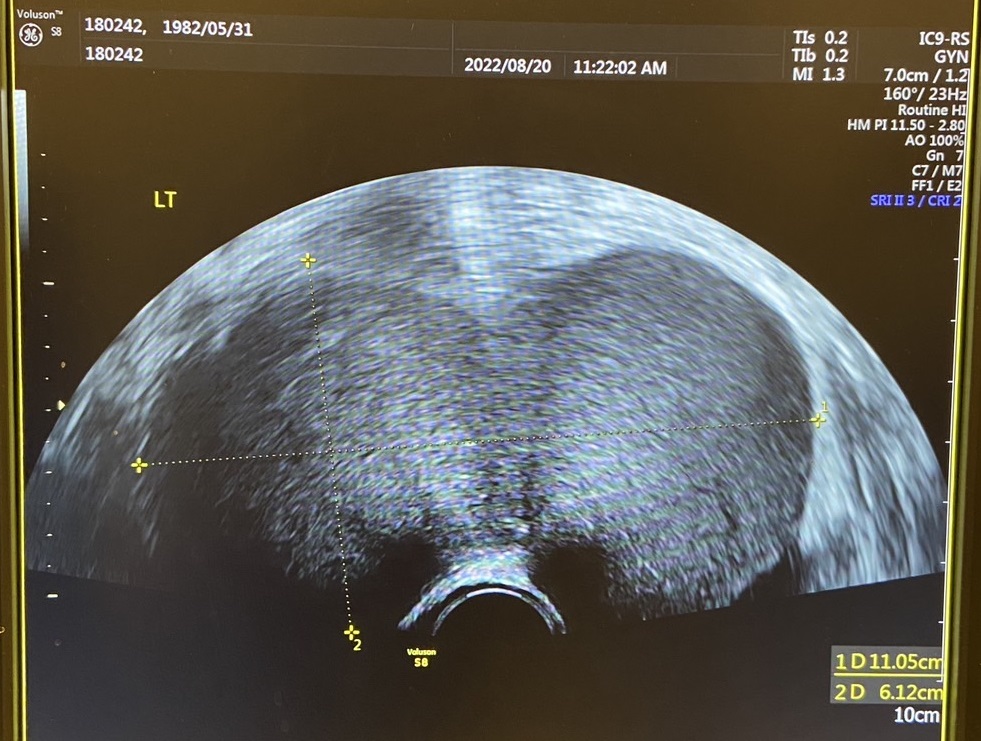

▲婦產科採「單孔微創手術」切除11公分「巧克力囊腫」

婦產科林于翔醫師說明,張小姐當時測得的腫瘤指數為672,正常值為<35 U/ml,但她卻已超出近20倍!超音波檢查發現卵巢左側有3顆巧囊,其中2顆是大的,另1顆小的被壓藏在大顆的下方,所以看起來很像1大顆的巧囊,總長度超過11公分、寬度6公分!故此,醫師採行「單孔腹腔鏡手術」予以切除,因她沾黏嚴重,所以又置放一條引流管,成功的手術讓腫瘤指數大幅下降至62。▲婦產科採「單孔微創手術」切除11公分「巧克力囊腫」